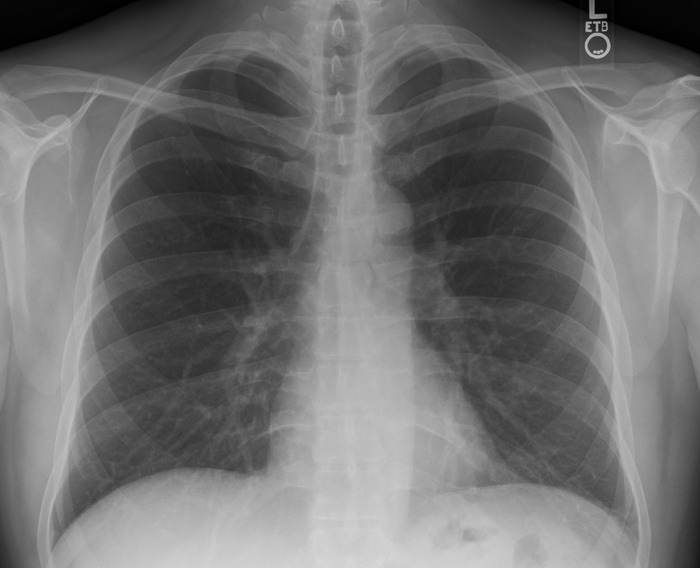

Расшифровка цифровых кодов флюорографии с примерами

01 - Кольцевидная тень (полость).

02 - Затемнение в легочной ткани (инфильтрация,ателектаз, округлая тень, среднедолевой синдром и др.).

03 - Очаговые тени в легочной ткани.

04 - Расширение тени средостения, в том числе увеличение размеров корня.

05 - Плевральные выпоты.

06 - Фиброзные изменения в легочной ткани (выраженные).

07 - Фиброзные изменения в легочной ткани (ограниченные).

08 - Повышение прозрачности легочной ткани (эмфизема локальная и распространенная).

09 - Изменения плевры (сращения, плевральные наслоения, обызвествления) выраженные.

10 - Изменения плевры (сращения, плевральные наслоения, обызвествления) ограниченные.

11 - Петрификаты крупные в легочной ткани - множественные (5 и более).

12 - Петрификаты крупные в корнях - множественные (5 и более).

13 - Петрификаты мелкие в легочной ткани - множественные (5 и более).

14 - Петрификаты мелкие в корнях - множественные (5 и более).

15 - Петрификаты крупные в легочной ткани - единичные.

16 - Петрификаты крупные в корнях - единичные.

17 - Петрификаты мелкие в легочной ткани - единичные.

18 - Петрификаты мелкие в корнях - единичные.

19 - Изменения диафрагмы, не связанные с плевральной патологией (диафрагмальная грыжа, высокое стояние диафрагмы и т. д.).

20 - Состояние после операции на легком.

21 - Изменения скелета грудной клетки (сколиоз, кифосколиоз, костная мозоль, добавочное ребро, остеофиты и т. д.).

22 - Инородное тело (проецируется на легочную ткань, тень средостения в мягких тканях).

23 - Сердечно-сосудистая патология.

24 - Прочие - добавочная доля.

25-норма.

25 - Норма.

26 - Брак.

Примечания:

При сочетании нескольких из перечисленных изменений каждое из них отмечается соответствующим кодом в каждой графоклетке.

Локализация, протяженность изменений отмечается дробью по второй графоклетке 1; 2; 3; 4; в числителе - правое легкое, в знаменателе - левое легкое (по полям).

Номер шифра легочных полей: 1 - первое, 2 - второе, 3 - третье, 4 - первое и второе, 5 - первое и третье, 6 - второе и третье, 7 - первое, второе и третье.

В третьей графоклетке вместо подписи врача подставляют личный номер рентгенолога.

Вызов на контрольное рентгеновское дообследование отмечается в четвертой графоклетке цифрой 1.